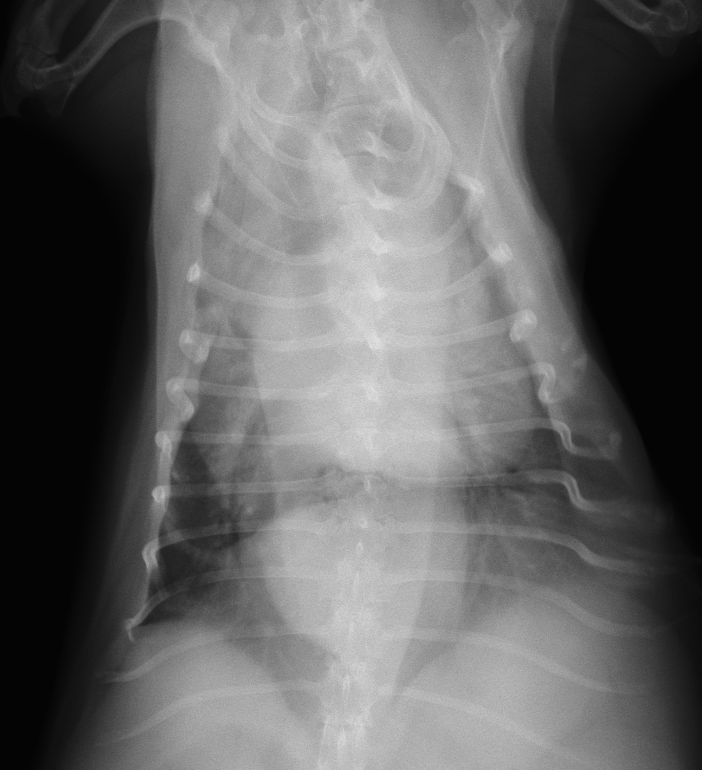

重度な巨大食道と誤嚥性肺炎のわんちゃん

重度な巨大食道と誤嚥性肺炎のわんちゃん